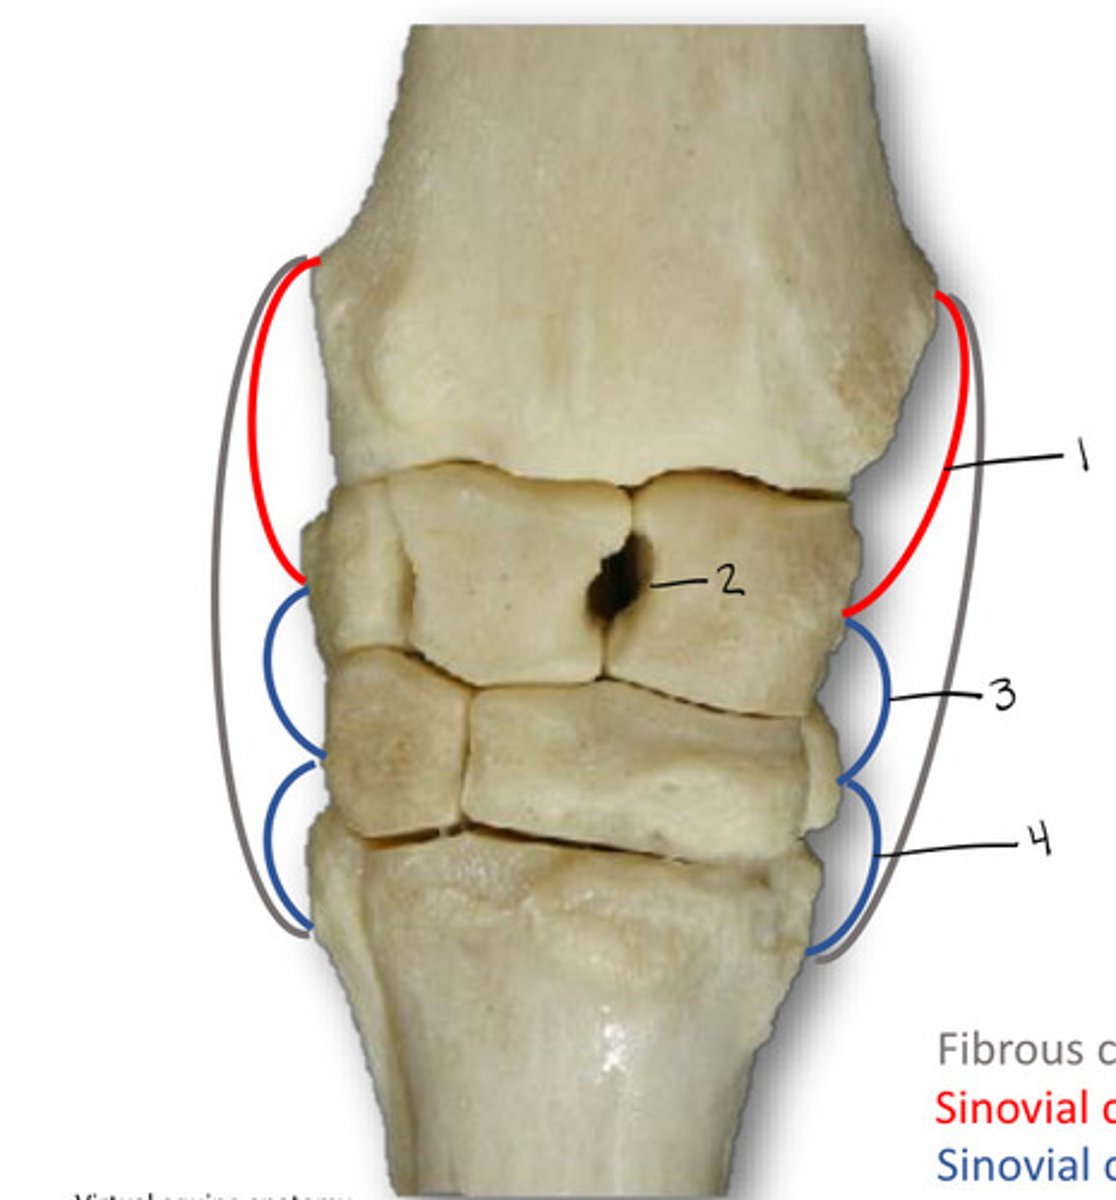

Radiocarpal

What is the joint labeled 1?

Intercarpal

What is the joint labeled 2?

Midcarpal

What is the joint labeled 3?

Carpomaetacarpal

What is the joint labeled 4?